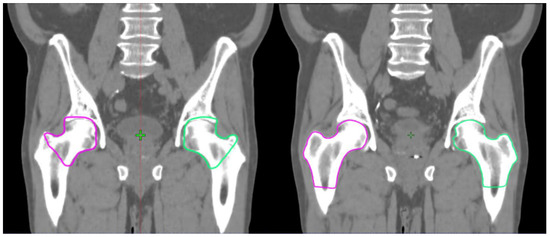

1. Introduction

2. Materials and Methods

2.1. DL Delineation Model

2.3. Contouring